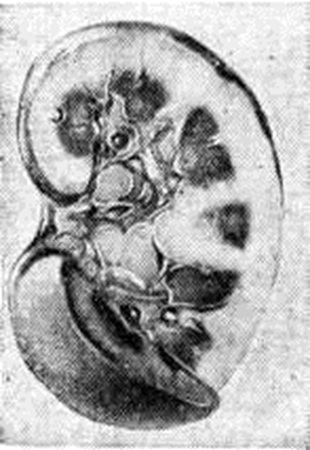

Рис. 4.

Электронограммы (а, в) и микропрепарат (б) почки при фокальном сегментарном гломерулярном гиалинозега — неровные контуры эндотелиальной поверхности базальной мембраны (указано стрелкой) гломерулярных капилляров (начальные изменения), × 15 000; б — гиалиновый материал (указан стрелками) в отдельных капиллярных петлях связан с капсулой клубочка; полутонкий срез, окраска метиленовым синим-азур II-фуксином, × 200; в — в цитоплазме мезангиальных клеток содержатся липиды (указано стрелкой), × 12 000.

Макропрепарат большой сальной почки: корковый слой значительно расширен, имеет светло-серый цвет.